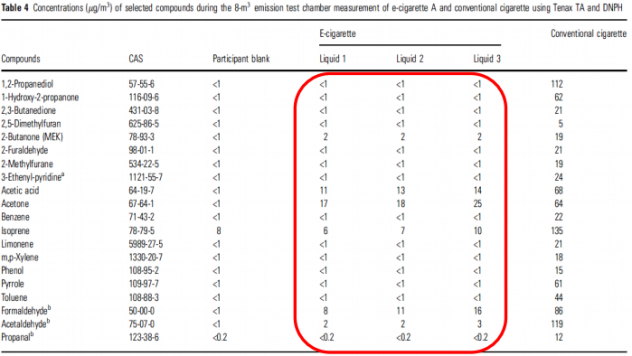

Командой Доктора Фарсалиноса был проведен интересный эксперимент, отвечающий на вопрос пассивного вейпинга. Они арендовали несколько одинаковых чистых гостиничных номера. В течение пяти часов в нескольких номерах парили по пять вейперов, а в других номерах пять специальных аппаратов, которых в рамках данного эксперимента можно приравнять к человеку, «курили» сигареты. В рамке отображено содержание вредных веществ в воздухе от трех разных жидкостей для электронных сигарет, а в правой — от обычных сигарет. В третьем столбце отображены данные до начала эксперимента.